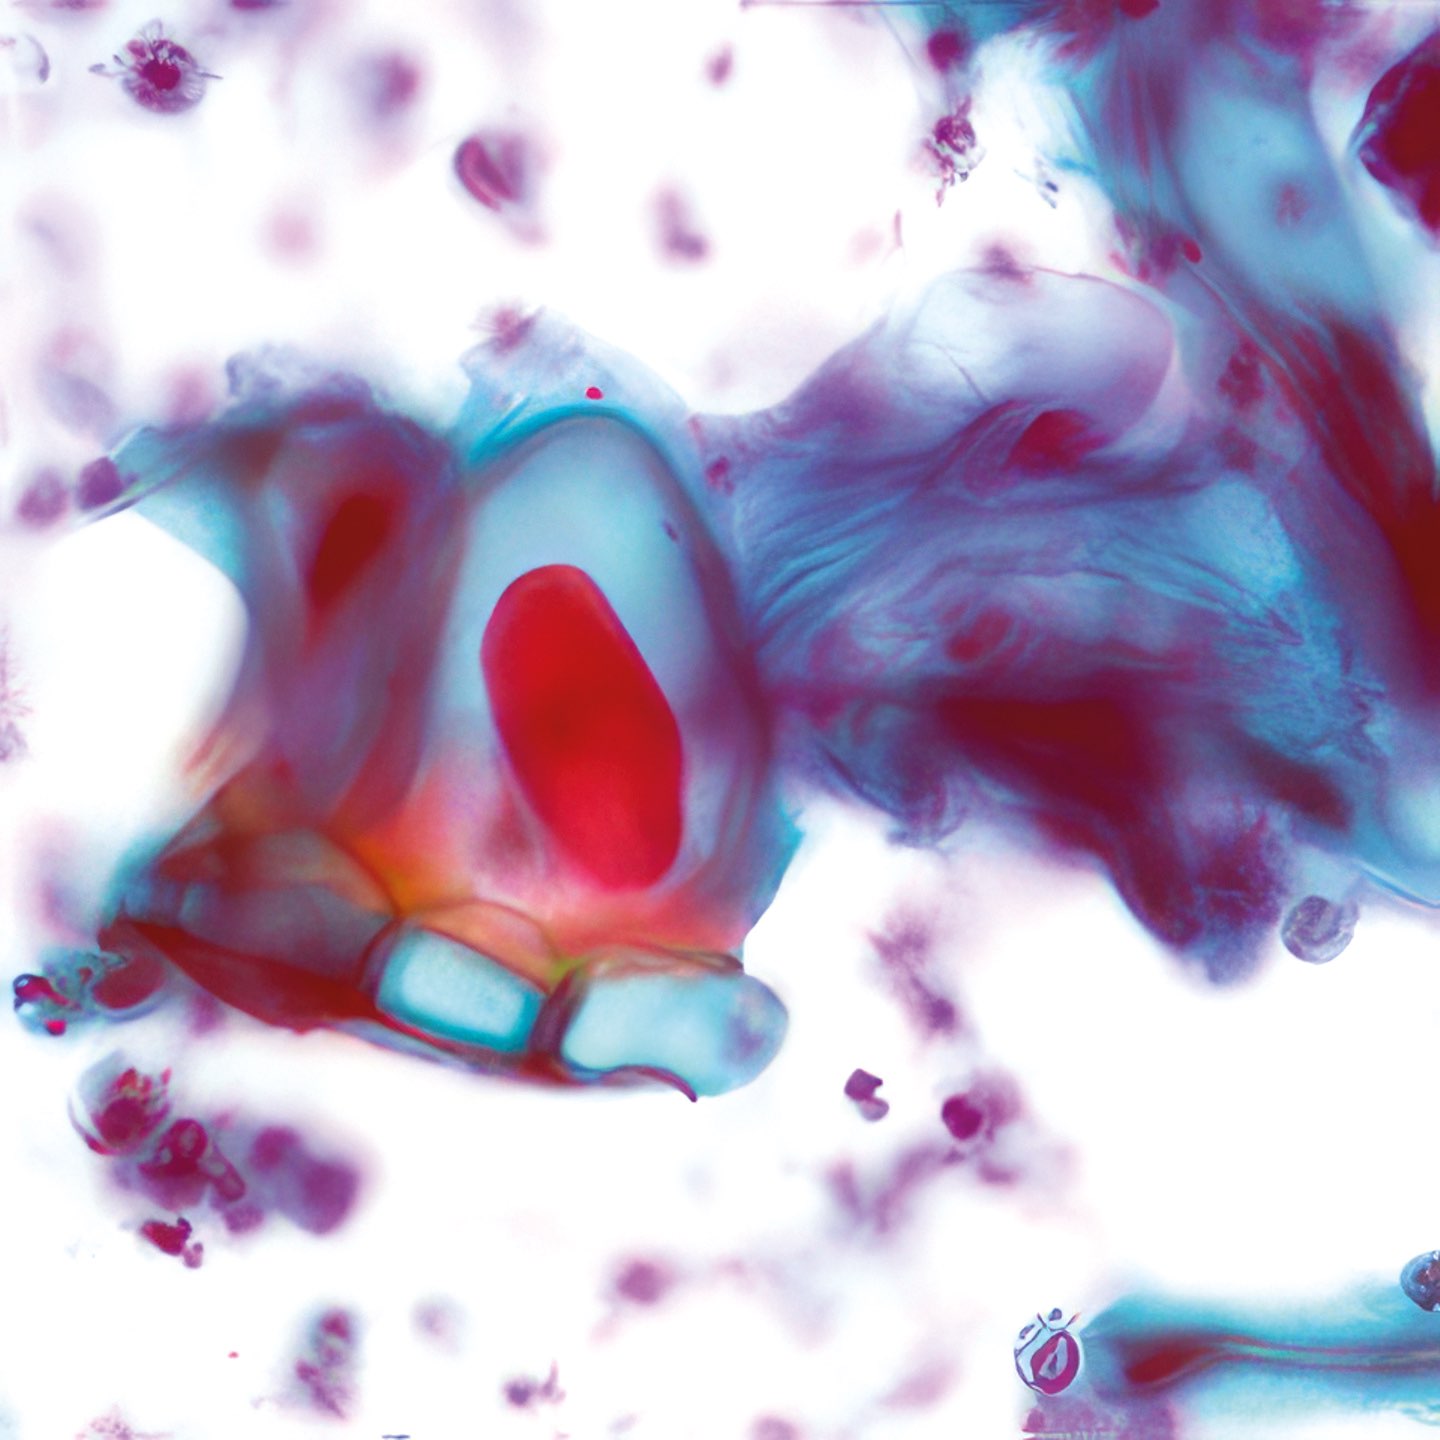

(Abbildungen 3 - 6: Pap, Vergrößerung 1000x)

Morbus Paget

Makroskopisch zeigt die areoläre Haut (Brustwarzenhof) eine feine ekzemartige nässende granuläre Struktur; die Brustwarze ist nicht eingezogen (Abb. 1 und 2). Die extrem atypischen Zellen liegen verstreut (Abb. 3), oder bilden lose zusammenhängende Gruppen (Abb. 4, 6). Einige sind doppelkernig. Im Vergleich zum gewöhnlichen Mammakarzinom sind sie extrem pleomorph und ihre Kerne sind stärker hyperchromatisch, sehr grob strukturiert, und zeigen manchmal prominente Chromozentren. Das Zytoplasma ist unterschiedlich breit und erscheint manchmal als vakuolär.

Histologie

Das durch Stanzbiopsie gewonnene histologische Präparat zeigt viele große, scheinbar vakuolisierte Zellen innerhalb des Plattenepithels. Eine PAS-Färbung war nicht möglich.

Differenzialdiagnose

Die zytologischen und histologischen Befunde sind charakteristisch für das Paget-Syndrom. Histologisch würden die Zellen PAS-positiv sein. Das Brustödem, die nicht eingezogene Brustwarze und die axilläre Schwellung weisen auf ein tiefsitzendes Karzinom hin, das bereits in die axillären Lymphknoten metastasiert hat. Die Kombination von Karzinom und Morbus Paget ist nicht ungewöhnlich 1. - Die extrem atypischen Zellen können zu einer Verwechslung mit einem Plattenepithelkarzinom führen 2. Andererseits unterscheidet dies die Zellen des Morbus Paget von denen des Adenoms, das ebenfalls in der areolären Region auftritt 3, 4. Schließlich können die makroskopisch erscheinenden vesikulären Strukturen einen Pemphigus vulgaris, eine Autoimmunerkrankung der Haut, simulieren 5.